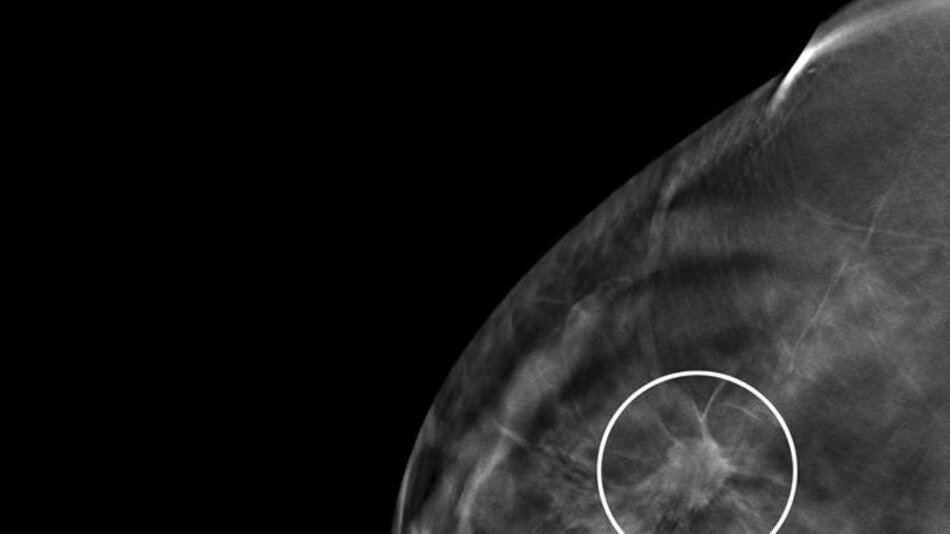

En el caso del cáncer de mama, Panamá sigue patrones de países no desarrollados en cuanto a la mortalidad. “Vemos mayor incidencia (porque hay más tamizaje), pero la mortalidad va subiendo”, dice Motta.

Al margen de la controversia que ha existido por años sobre la efectividad de las mamografías, Motta destaca que en las provincias y áreas remotas el acceso a una mamografía no es tan fácil, y cuando se hace un diagnóstico tarde, cuando ya la mujer tiene metástasis, la probabilidad de sobrevivencia se reduce. “Creo que es un efecto de inequidad y diagnóstico tardío”.

Al respecto, el oncólogo médico Juan Pablo Barés, presidente de Fundacáncer y otro de los autores de este trabajo, señala que faltan más datos para investigar a fondo el cáncer de mama. “No tenemos elementos importantes, por ejemplo, ¿cuántos pacientes de cáncer de mama, en diferentes estadios, se han detectado en el país? Tenemos un subregistro”.“Contamos con las mismas herramientas de tratamiento de países desarrollados, en Panamá hay excelentes cirujanos, oncólogos médicos, radiooncólogos, medicinas, etc., ¿por qué no vemos una reducción en la mortalidad?

Uno de los aspectos que resalta, y en eso coincide con Motta, es que no todas las pacientes tienen el mismo acceso a la tecnología de diagnóstico. “En Panamá no en todos los lugares hay mamógrafos. No en todos los lugares donde los hay se encuentra un especialista para interpretar las mamografías. Y no en todos los lugares se le puede hacer una biopsia expedita a las pacientes. Puede tomar un mes, tres meses. Todo esto afecta el diagnóstico”.